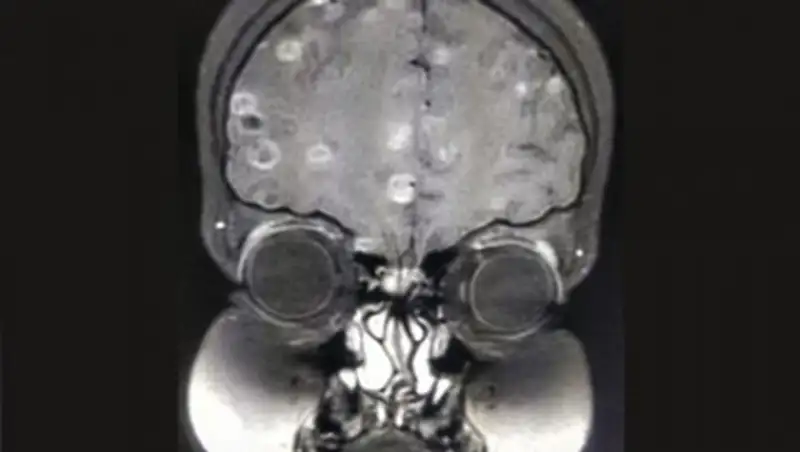

Полгода спустя отчаявшиеся родители отвели ее к другому доктору. Снимок мозга показал, что ребенок страдает цистицеркозом головного мозга, то есть в ее голове находятся личинки свиного цепня. Врачи предполагают, что девочка заразилась ими либо из-за немытых фруктов и овощей, либо из-за недоваренной свинины. В кишечнике личинки внедрились в стенку кишки и через кровеносную систему добрались до мозга.